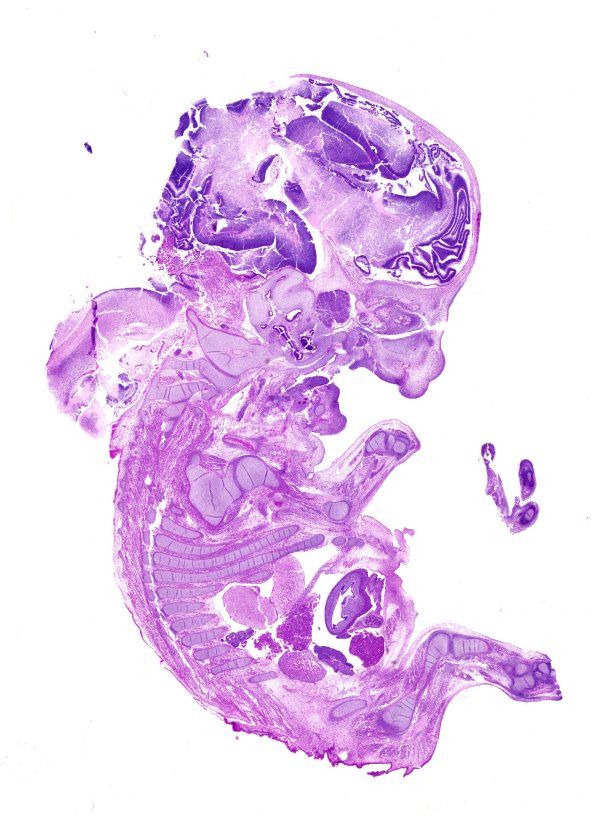

Washington University Experience | DEVELOPMENTAL MALFORMATIONS | Encephalocele | 1B1 Myelomeningocele (Case 1) H&E WM

1B1,2 A sagittal histologic section shows the encephalocele which contains intracranial contents. The site of origin of the encephalocele appears to represent the junction of the cranium and vertebral column. (H&E)